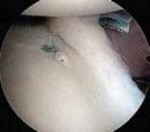

Anchor Placement and Capsulolabral Plication

With the glenoid prepared and the tissue mobilized, fixation begins at the most inferior aspect of the lesion, typically at the 5:30 or 6 o'clock position. Modern fixation relies on either biocomposite or all-suture anchors, typically 1.5 mm to 2.9 mm in diameter. The drill guide is introduced through the anteroinferior portal, and the anchor is deployed on the articular margin (1-2 mm onto the articular cartilage face) to recreate the anatomical labral bumper. The trajectory of the drill is paramount; it must be directed slightly medially to avoid penetrating the articular surface of the glenoid vault.